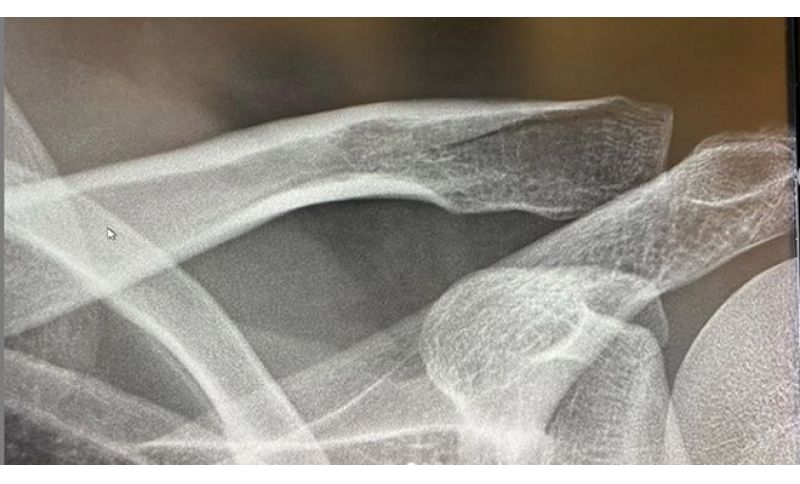

Sfortunato anche il ligure Oliviero Troia che sabato scorso, alla Omloop Het Nieuwsblad è stato convolto in una maxi caduta che gli è costata la frattura della clavicola. E sui social il corridore della UAE Team Emirates ha scritto: “Non è uno dei più fortunati inizi di stagione, per me. Purtroppo sabato sono rimasto coinvolto in una caduta e ho riportato una frattura della clavicola sinistra! A malincuore mi tocca un altro mese di stop!” (nella foto le lastre).